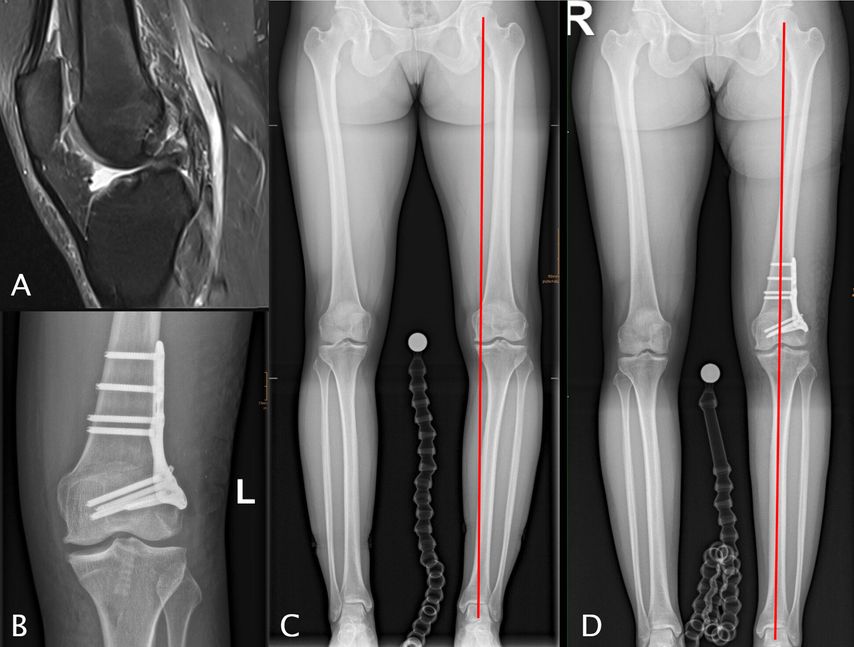

Knöcherne Achsfehlstellungen der unteren Extremität beeinflussen die Biomechanik des Kniegelenks maßgeblich und stellen relevante Risikofaktoren für Rupturen des vorderen Kreuzbandes (VKB) sowie für das Versagen von VKB-Rekonstruktionen dar. Insbesondere im Revisionssetting rücken sagittale und koronare Fehlstellungen zunehmend in den Fokus der differenzierten Therapieplanung.